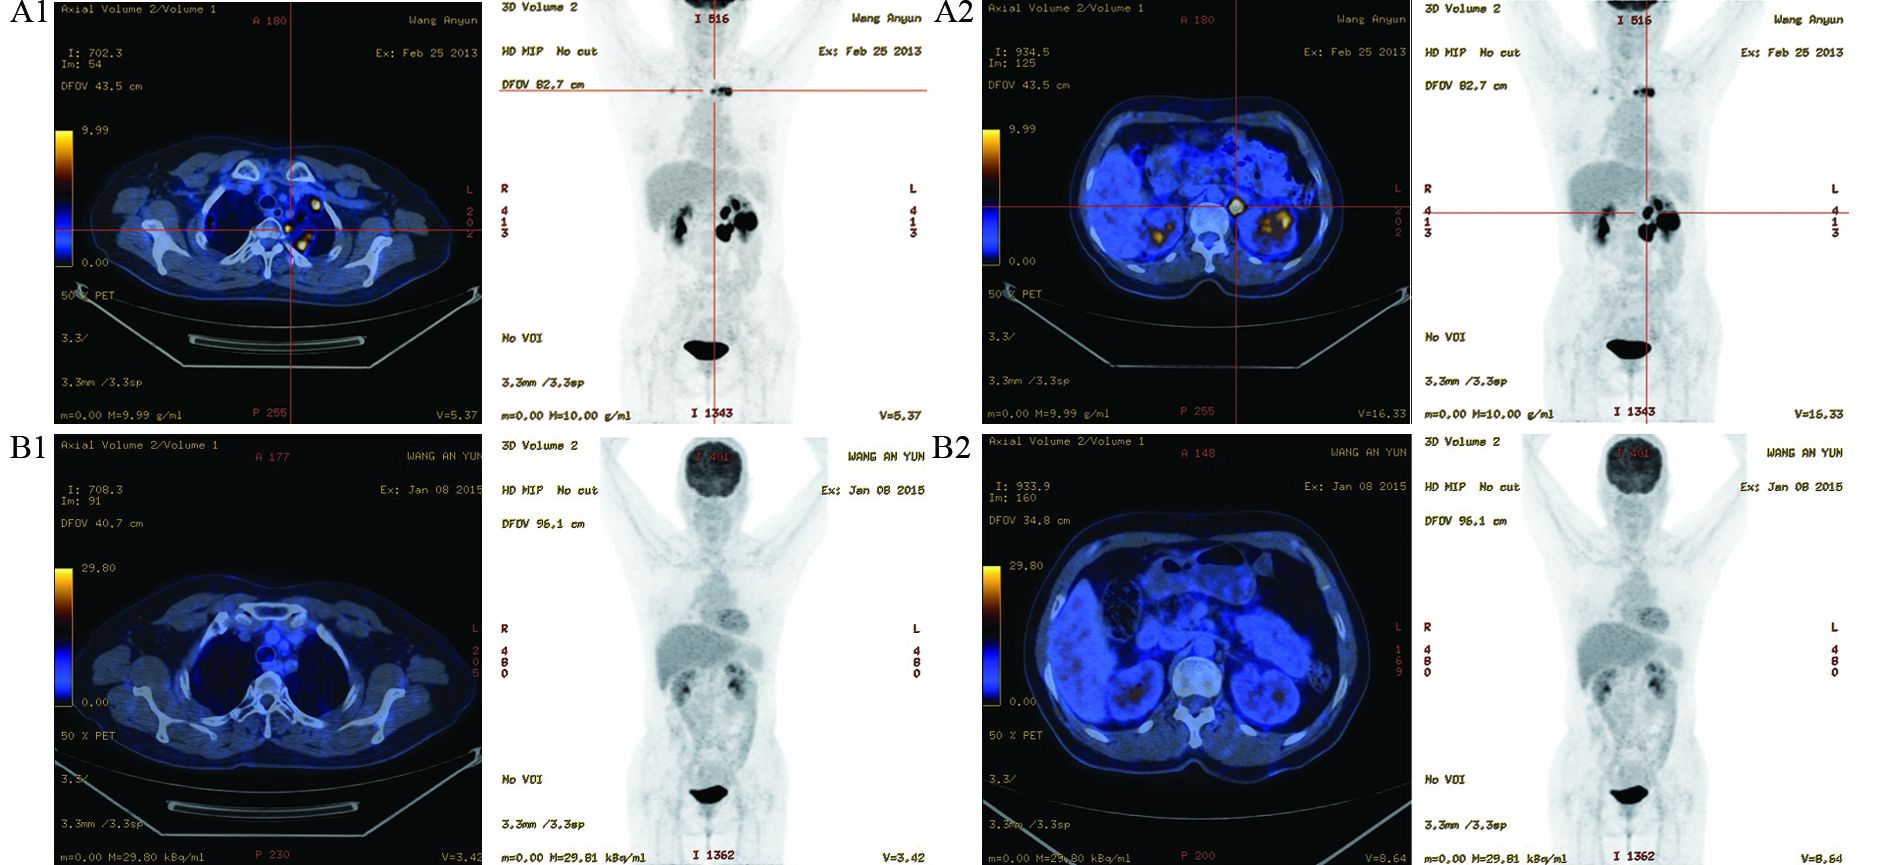

患者于2012年12月因“左腰部疼痛”再次就诊。完善PET-CT检查,结果示:左肾外缘及腹膜后分别见一枚结节状高代谢病灶,考虑淋巴瘤浸润(SUVmaxV别为:17.8,24.47;大小分别为3.1 cm×2.1 cm,2.5 cm×1.8 cm);两肺上叶炎性病变;鼻咽局部未见肿瘤残留征象。复查骨髓细胞学正常,血清LDH水平正常。临床诊断NHL复发,aaIPI:1分。于2012年12月19日—2013年1月15日给予R-CEOP(利妥昔单抗375 mg/m2,1 d;环磷酰胺750 mg/m2,1 d;依托泊苷100 mg/m2,3 d;长春新碱1.4 mg/m2,1 d;强的松片100 mg/d,5 d)方案化疗2周期,复查PET-CT:原左肾结节较前增大(SUVmaxV18,大小约3.7 cm×3.0 cm);腹膜后可见两枚结节病灶(较大一枚SUVmaxV21.62,大小约2.5 cm×2.0 cm);两肺上叶多发结节,代谢增高,考虑淋巴瘤肺浸润(SUVmaxV12.86,最大结节约1.4 cm×1.4 cm);鼻咽仍未见明显恶性肿瘤征象,见图 1。CT引导下肺部结节穿刺活检,提示DLBCL。免疫组织化学结果示:CD20(+),LCA(+),Bcl-2(+),Mum-1(+),Bcl-6(+),CD3(-),CD10(-),Ki-67约70%,见图 2。

| A1: chest; A2: abdomen; B1: chest; B2: abdomen 图 1 R-CEOP(A)和ABVD(B)方案化疗后的PET-CT结果 Figure 1 PET-CT result after R-CEOP(A) and ABVD(B) regimen chemotherapy |

结合两次病理活检结果,本例患者诊断:难治性DLBCL,Ⅳ期。患者病情继续进展。于2013年3月14日—4月18日给予GemOx方案(吉西他滨:800 mg/m2,d1,d8;奥沙利铂:85 mg/m2,d1)化疗2周期,复查CT示肺部结节缩小减少,腹膜后及左肾病灶无明显变化。继续GemOx方案化疗1周期,患者腰痛症状明显加重,复查腹部CT示腹膜后及左肾病灶明显进展。此时患者一般状况较差,ECOG评分2分,于2013年6月1日开始给予ABVD方案(吡柔比星:25 mg/m2,d1,d15;博来霉素,10 mg/m2,d1,d15;长春新碱,1.4 mg/m2,d1,d15;氮烯咪胺,375 mg/m2,d1,15)化疗4周期,1周期后腰痛症状缓解,2周期后评估疗效CR。于2015年1月8日复查PET-CT仍未见明显高代谢病灶。随访至2016年7月27日,该患者仍是缓解状态,缓解持续时间超过2年。该患者拒绝行造血干细胞移植,目前仍在随访中。